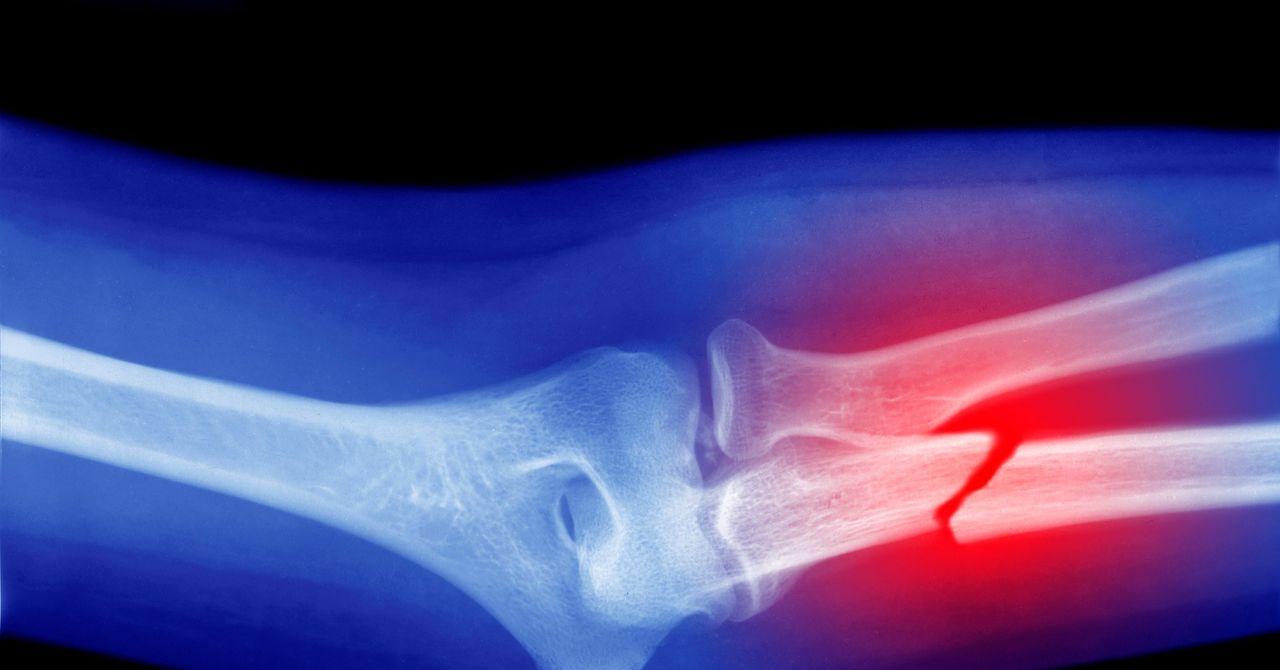

Esta combinación de efectos genera un desequilibrio que acelera el debilitamiento de la estructura ósea. Los estudios en animales también sugirieron que la acumulación de microplásticos en el cuerpo puede disminuir el recuento de glóbulos blancos, lo que indica alteraciones en la función de la médula ósea. Además, se asoció el impacto de los microplásticos en los osteoclastos con un deterioro de la microestructura ósea y un aumento del riesgo de fragilidad, deformidades y fracturas.

Los investigadores advierten que el impacto potencial de los microplásticos en los huesos no es despreciable y podría contribuir al aumento proyectado de fracturas óseas. Los microplásticos y nanoplásticos, fragmentos diminutos de plástico, se han detectado en todo el mundo y en el cuerpo humano. La producción masiva de plástico y su bajo índice de reciclaje contribuyen a su dispersión en el medio ambiente, lo que subraya la urgencia de reducir su uso.